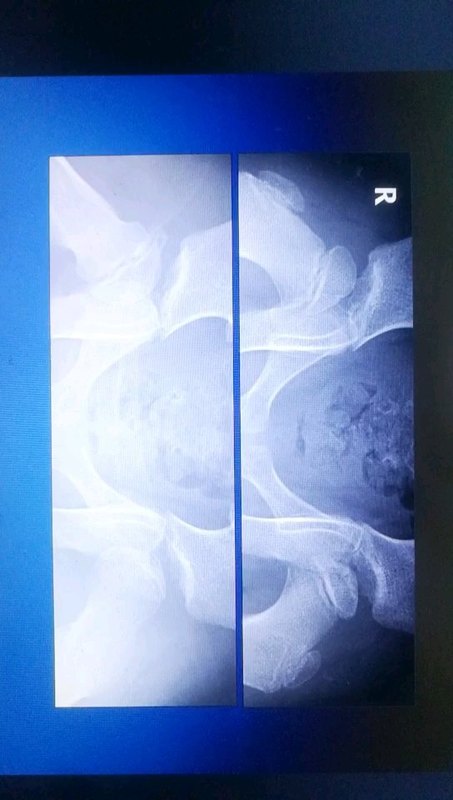

Perthes 病科普系列之二:儿童股骨头坏死如何分期

张中礼主任医师 天津医院 小儿骨科

3338人已读